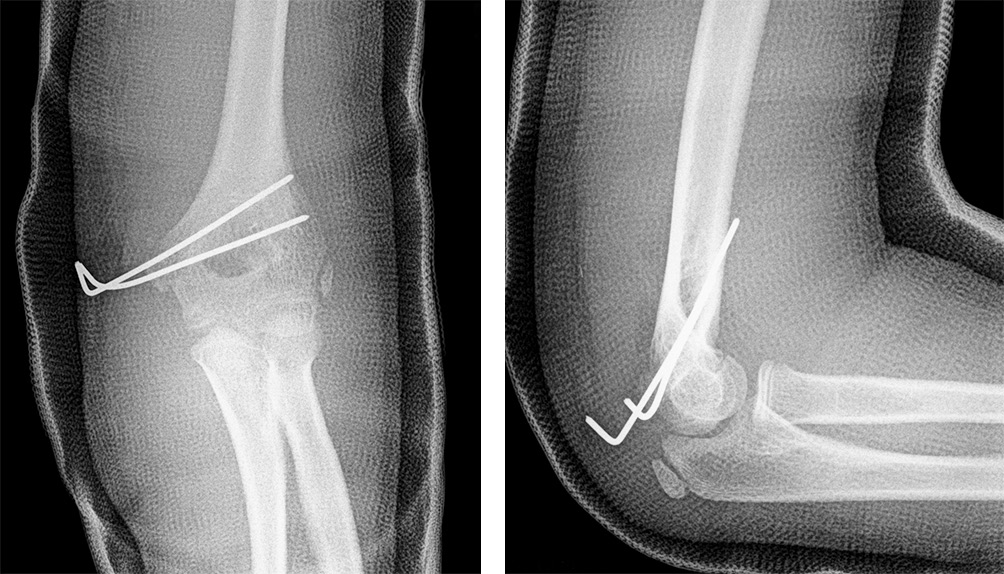

Fig. 4. Patient S. The post-operative X-ray shows the ME fixed with two crossing bicortical 1.5 mm K-wires